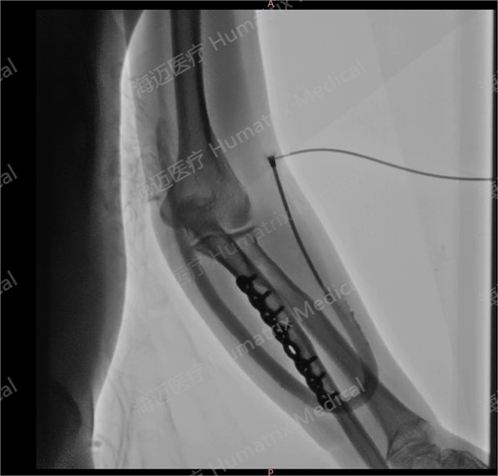

臨床試驗患者使用LineMatrix耐邁通?生物型人工血管長期血液透析,血管造影通暢。

臨床隨訪結果顯示,產(chǎn)品完成植入后,患者術后3月初級通暢率90.9%,累積通暢率100%;術后6月初級通暢率80.8%,累積通暢率100%。人工血管未引發(fā)人體免疫反應,無感染及動脈瘤等并發(fā)癥發(fā)生,產(chǎn)品性能明顯優(yōu)于ePTFE人工血管,臨床效果優(yōu)異。